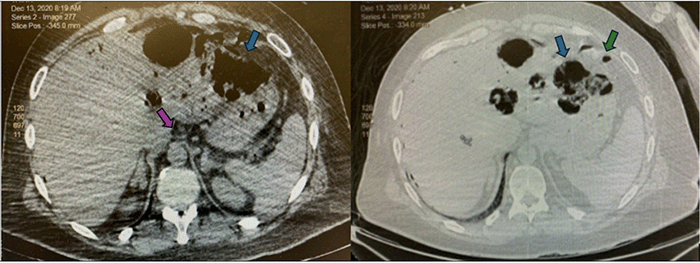

Figure 3. Post-Intervention CT Demonstrating Hepatic Abscess and Drain Placement. Published with Permission.

Axial contrast-enhanced CT scan of the abdomen obtained POD 4. The image shows resolution of the previously noted pneumoperitoneum. A well-defined fluid collection consistent with an abscess is now evident in the left hepatic lobe. Note the presence of a newly placed percutaneous interventional radiology drain within the hepatic abscess (left-sided drain) and the surgically placed intra-abdominal drain (right-sided drain)